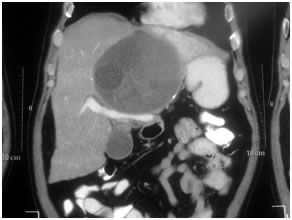

HCC in a non cirrhotic liver

Large HCC in seg 2 & 3

Large HCC in seg 2&3